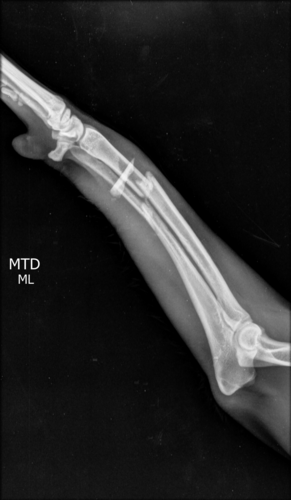

Infelizmente no dia 15/04 ele foi vítima de um atropelamento, como consequência teve fratura no maxilar e na patinha, e também está com processo inflamatório no pulmão!Os tutores não tem condições para arcar com todos os gastos, porque além disso tudo, o dono/companheiro do Campeão é portador do Autismo, e ele precisa URGENTEMENTE do seu melhor amigo em casa novamente!A cirurgia das fraturas está no valor de $3000. Além disso ele precisa de internação e controle com medicação no pós cirurgico.